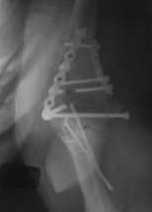

Подскажите пожалуйста, как можно в дальнейшем этому больному помочь. В марте первая

операция, пришлось оперировать на 16 сутки в виду инфицированных садин и анемии. Заживление

первичным натяжением, ранняя разработка после операции, а через 2 нед болевой синдром,и

постепенно движения в локтевом суставе ограничились до полного анкилоза. Повторно через 4

месяца вторая операция - артролиз, удаление оссификатов, удаление фиксаторов,

реостеосинтез этой же реконструкционной пластиной и винтом. Интраоперационно после

удаления оссификатов и фиксаторов обнаружил, что переломы не сросшиеся, поэтому пришлось

синтезировать заново. Зажила рана первично, объем движений в локтевом суставе сгибание 70,

разгибание160, ротационные движения востановились полностью, вроде бы успокоились.

Опять постепенно в течении 8 нед после повторной операции постепенно движения ограничились

до 80 - 110, на снимке оссификат. Снимки во вложении, буду рад Вашим советам. Спасибо!